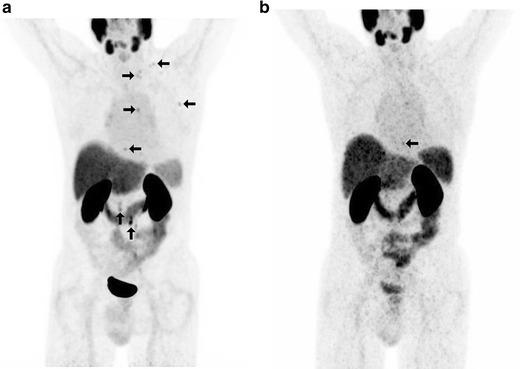

In 14 selected patients with PSA relapse of prostate cancer, [(18)F]DCFPyL PET/X-ray computed tomography (CT) was performed in addition to [(68)Ga]Ga-PSMA-HBED-CC PET/CT. A systematic comparison was carried out between results obtained with both tracers with regard to the number of detected PSMA-positive lesions, the standardized uptake value (SUV)max and the lesion to background ratios.

RESULTS

All suspicious lesions identified by [(68)Ga]Ga-PSMA-HBED-CC were also detected with [(18)F]DCFPyL. In three patients, additional lesions were observed using [(18)F]DCFPyL PET/CT. The mean SUVmax in the concordant [(18)F]DCFPyL PSMA-positive lesions was significantly higher as compared to [(68)Ga]Ga-PSMA-HBED-CC (14.5 vs. 12.2, p = 0.028, n = 15). The mean tumor to background ratios (n = 15) were significantly higher for [(18)F]DCFPyL compared to [(68)Ga]Ga-PSMA-HBED-CC using kidney, spleen, or parotid as reference organs (p = 0.006, p = 0.002, p = 0.008), but no significant differences were found using the liver (p = 0.167) or the mediastinum (p = 0.363) as reference organs.

CONCLUSION

[(18)F]DCFPyL PET/CT provided a high image quality and visualized small prostate lesions with excellent sensitivity. [(18)F]DCFPyL represents a highly promising alternative to [(68)Ga]Ga-PSMA-HBED-CC for PSMA-PET/CT imaging in relapsed prostate cancer.

在14例选定的前列腺癌PSA复发患者中,除了进行[(68)Ga]Ga-PSMA-HBED-CC PET/CT外,还进行了[(18)F]DCFPyL PET/X射线计算机断层扫描(CT)。对两种示踪剂获得的结果在检测到的PSMA阳性病变数量、标准化摄取值(SUV)最大值和病变与背景比值方面进行了系统比较。

结果

[(68)Ga]Ga-PSMA-HBED-CC识别出的所有可疑病变也能用[(18)F]DCFPyL检测到。在3例患者中,使用[(1)F]DCFPyL PET/CT观察到了额外的病变。与[(68)Ga]Ga-PSMA-HBED-CC相比,[(18)F]DCFPyL PSMA阳性病变中的平均SUV最大值显著更高(14.5对12.2,p = 0.028,n = 15)。以肾脏、脾脏或腮腺作为参考器官时,[(18)F]DCFPyL的平均肿瘤与背景比值(n = 15)显著高于[(68)Ga]Ga-PSMA-HBED-CC(p = 0.006,p = 0.002,p = 0.008),但以肝脏(p = 0.167)或纵隔(p = 0.363)作为参考器官时未发现显著差异。

结论

[(18)F]DCFPyL PET/CT提供了高质量的图像,并以优异的灵敏度显示了小的前列腺病变。对于复发前列腺癌的PSMA-PET/CT成像,[(18)F]DCFPyL是[(68)Ga]Ga-PSMA-HBED-CC极具前景的替代物。